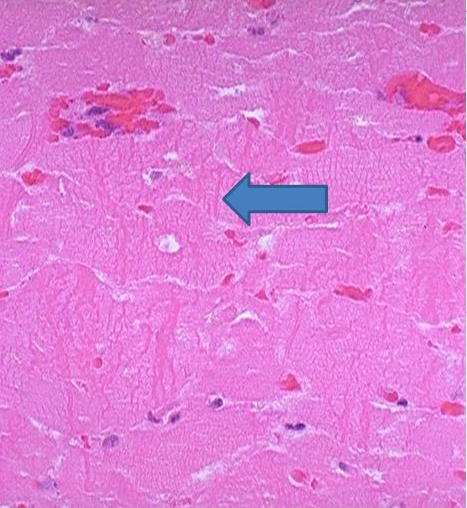

When would this histopatholigcal slide from an MI likely to have occurred

Less than 1 day

Less than 7 days accute inflam

1-3 week

3-6 weeks